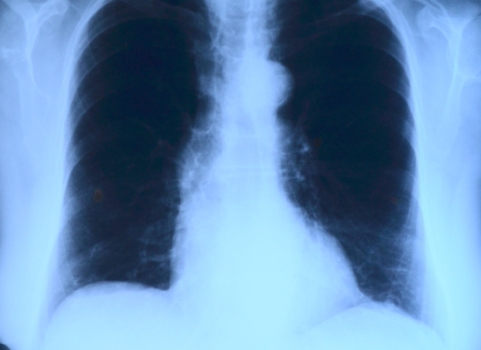

폐결절 발견 빠른 대응이 필요할 때 2023-12-052023-12-05 by paranstar 폐결절 발견 시 빠른 대응이 왜 중요할까요? 이 글에서는 그 이유를 알아보겠습니다. 폐결절 발견시 초기 대응 요령 폐결절이란 폐에 생긴 … Read more